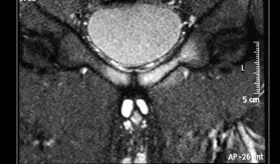

El hematoma comprimía la médula espinal y fue causado por sangrado arterial, no venoso, lo cual es poco común en estos casos.